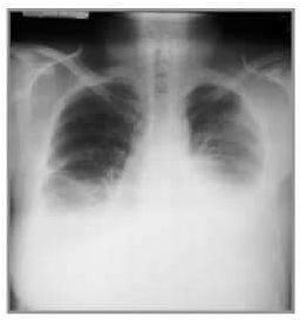

32/M came in 30 minutes post-injury, Shot by unknown assailant PE: BP 100/60 HR 130 RR 20 Neuro exam: GCS 15 Chest: (+)GSW 4th ICS left MCL, 5th ICS r midscapular line decreased breath sounds below lower lungs Distinct heart sounds Abdomen: soft, nontender

Sounds like he’s starting to go into hypovolemic shock, need to increase O2 saturation, restore blood flow putting him on a blood& fluids bag. Looks like there’s also a lot of fluid building up in the chest cavity, finding the source and watching out for clotting would be good.